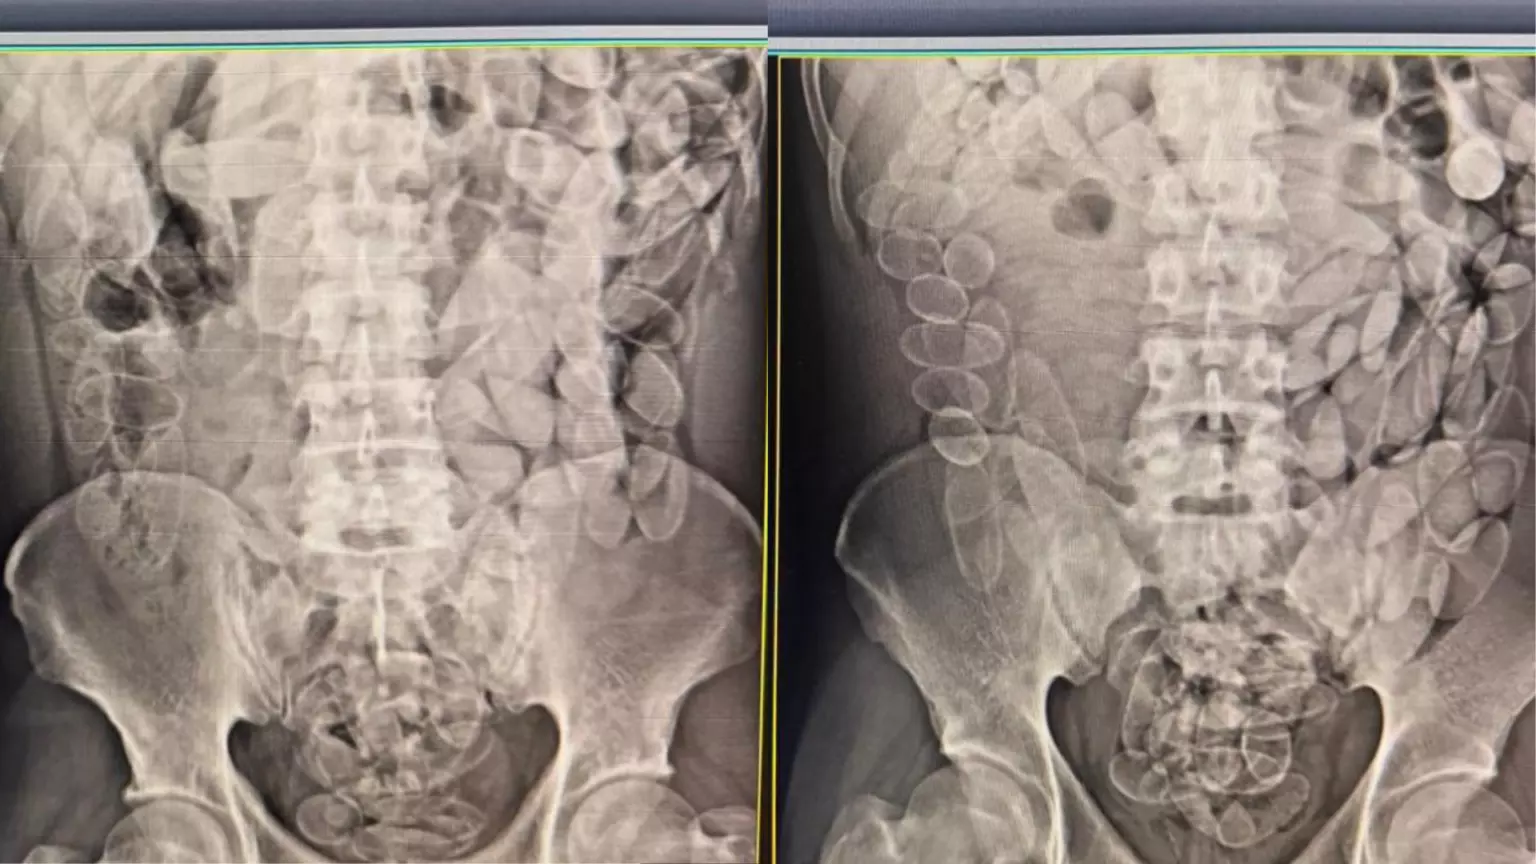

Diante da situação, o trio foi encaminhado a uma unidade hospitalar. Exames de imagem confirmaram que cada um havia ingerido aproximadamente 100 cápsulas contendo a droga. Após a realização dos procedimentos médicos para a expulsão dos entorpecentes, os três foram encaminhados à Delegacia da Polícia Federal, onde permanecerão à disposição da Justiça.